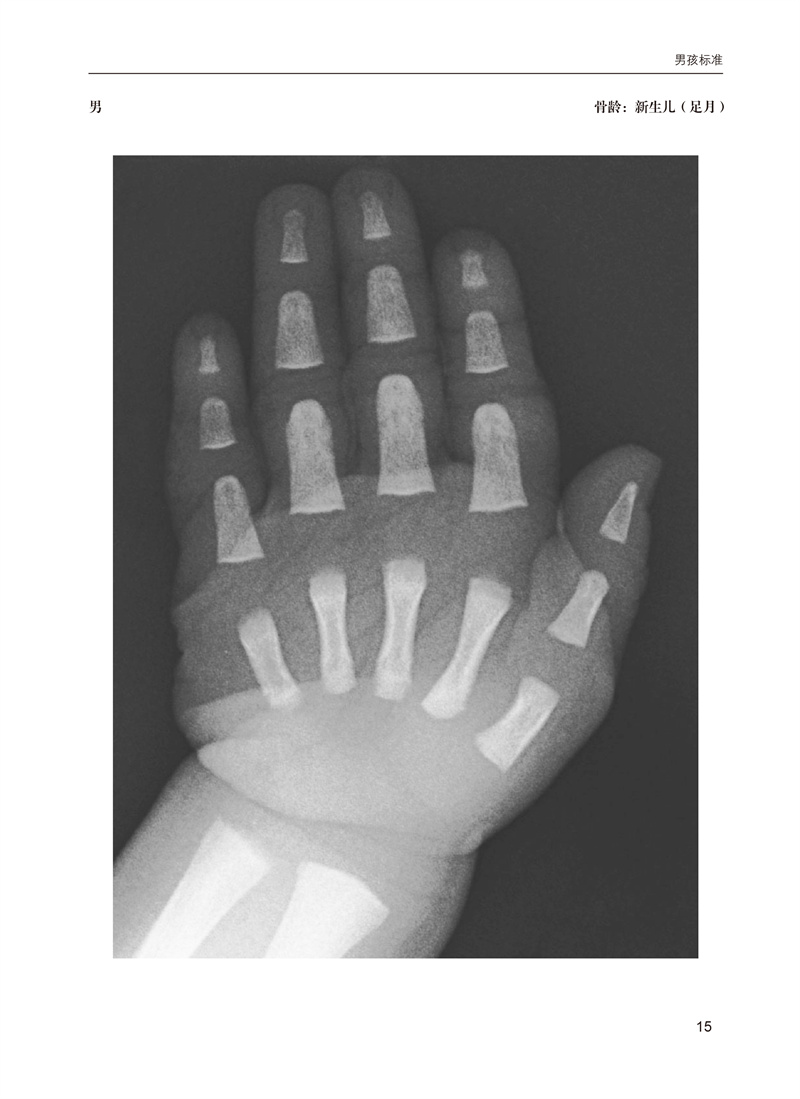

骨龄是国际公认的准确反应儿童生长发育的重要指标,也是临床医学、体育及法医学领域不可或缺的一项重要检查。本书基于广受欢迎的Greulich和Pyle图谱,将儿童骨骼成熟度的确定方法现代化。它提供了大量的图像,这些图像是从弗吉尼亚大学的PACS中的数千张数字X光片中精心挑选出来的,以最佳展示重要发育性骨特征,并按年龄和性别组织,以便快速参考。为了便于学习和临床图像分析,带注释和不带注释的图像成对出现,以便容易比较。图像上的简洁注释取代了冗长的文本,以提供更快速、更清晰的骨骼年龄标志。这些注释强调了重要而微妙的特征,帮助区分否则看起来相似的图像。本书分为两大部分:男性和女性各年龄段标准图谱。本书是一个高质量的左手腕X线片标准图谱,捕捉了Greulich和Pyle公认标准的重大和细微细节。鉴于骨龄应用的广泛性,手和腕部骨骼发育不仅旨在为实践和培训放射科医生提供参考,也适用于所有将骨龄研究作为实践一部分的人员。